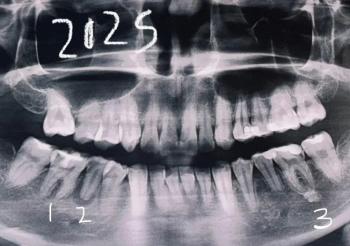

This close-up image shows fixed orthodontic braces with elastic chains (power chains) engaged across multiple brackets. Elastic chains are commonly used to close spaces and consolidate tooth alignment. Mild plaque accumulation is visible around brackets and wire, which is typical during active orthodontic phases and requires focused hygiene.

Full Analysis and Diagnosis

Probable Diagnosis

Orthodontic treatment in elastic chain phase

Appliance-associated plaque accumulation

(Clinical confirmation recommended.)